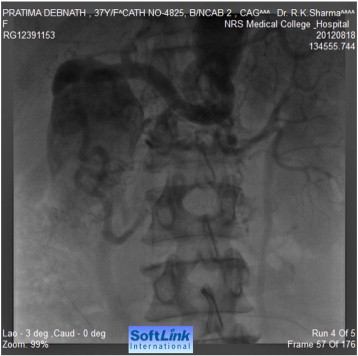

Tran-femoral catheter passage beyond the bifurcation of the abdominal aorta was not possible due to total occlusion and trans-radial aortic angiography showed a long segment of total occlusion (coarctation of abdominal aorta) just below the origin of both renal arteries, multiple dilated collaterals connecting both upper and lower aortic segments with a huge aneurysm involving gastroduodenal artery (Fig. 2, Fig. 3 ;  Fig. 4). Lower thoracic aorta was calcified and arch vessels origins and proximal aorta were normal. The blood pressure within the aneurysm was 190/110 mmHg (Fig. 5).

Abdominal aorta after the coarctation segment and iliac arteries.

Fig. 3.